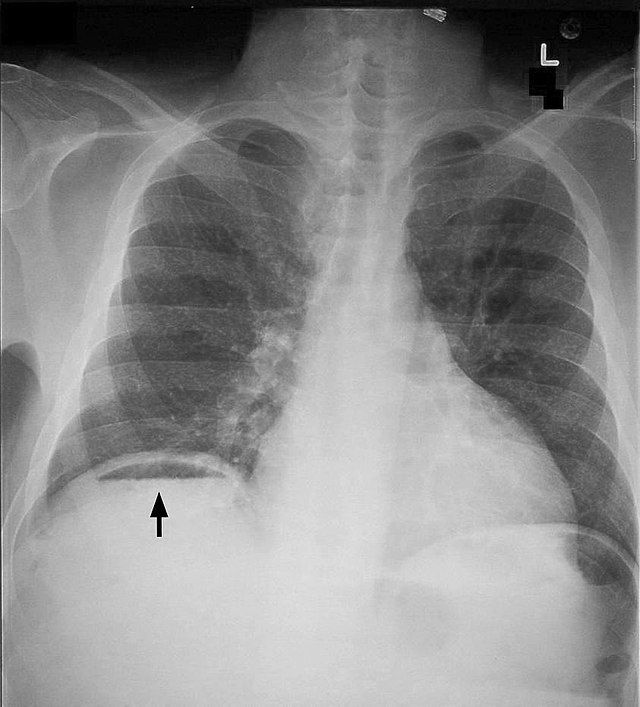

Example 2

Take a look at the following example showing consolidation. Click on the box to reveal the diagnosis.

Diagnosis

Left sided Tension Pneumothorax

Image 2: Gaillard, F. Tension pneumothorax. Case study, Radiopaedia.org. (accessed on 11 Oct 2022) https://doi.org/10.53347/rID-10558